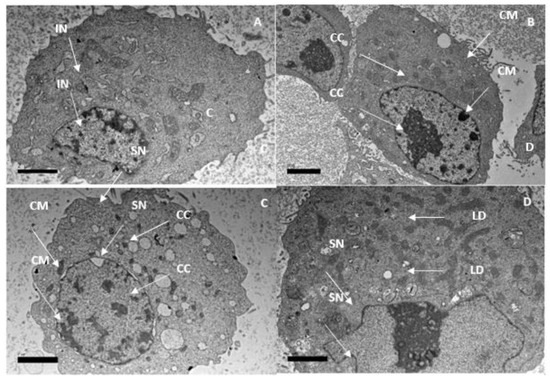

Additionally, using a scanning electron microscope, we observed structures similar to vacuoles in the cytoplasm of the cells (Figure 11), while cytoplasmic fragmentation was observed using a transmission microscope (Figure 12). These alterations became more pronounced with longer exposure times and resembled those induced in the human melanoma cell line (HT-144) after 48 h of incubation with cinnamic acid, a similar pro-apoptotic compound to our compound [18]. Additionally, after 48 and 72 h of incubation with IC50 concentrations of 7-geranyloxycinnamic acid, enlarged cytoplasm, presence of blebs and vacuoles, and loss of plasma membrane were observed under both electron microscopes. The integrity of the cell membrane was also harmed by the 7-geranyloxycinnamic acid after 48 and 72 h of incubation, as demonstrated by a transmission electron microscope (Figure 12). Thus, it is clear from the SEM and TEM analyses that 7-geranyloxycinnamic acid treatment of MCF-7 cells at the IC50 concentration caused a considerable rise in the cellular retraction over time, along with alterations in cell contours and loss of connections between MCF-7 cells. 7-geranyloxycinnamic acid was found to exert a profound cytotoxic effect only when cells were exposed to 48 and 72 h with IC50 concentration and showed substantial morphological changes since the majority of dead MCF-7 cells were at late apoptotic stage and had lost their membrane integrity (red fluorescent color) (Figure 13).

Figure 12.

TEM for MCF-7 cell line. (A) control, (B) treated cells 24 h, (C) 48 h and (D) 72 h, respectively. IN, Intact nucleus; CC, chromatin condensation; CM, chromatin margination; SN, shrinkage of nuclei; LD, lipid droplet.

In addition, 7-geranyloxycinnamic acid at IC50 concentration promoted profound morphological changes in MDA-MB-231 after 24, 48, and 72 h of incubation as evidenced using scanning electron microscopy (Figure 15), transmission electron microscopy (Figure 16), and fluorescent microscopy analyses (Figure 17). From the TEM images, we can clearly see the cell retraction and presence of structures similar to vacuoles inside the cytoplasm, which became denser and more stained with yellow then red color with increasing exposure time, as seen from fluorescent microscopic images. SEM observations revealed changes in cell shape and disruptions at cell junctions that support the separation of nearby cells (Figure 15). Nuclear changes were also observed; as a result, the nucleus got denser and slightly shifted towards periphery (Figure 16). From the TEM morphological studies, it was clearly evident that MDA-MB-231 cells showed apoptotic features following 72 h of treatment with 7-geranyloxycinnamic acid at IC50 concentration. In addition, after being exposed to 7-geranyloxycinnamic acid for 48 and 72 h, the MDA-MB-231 cells displayed the presence of blebs and an increase in cytoplasmic size.

Apoptosis is the cells’ natural mechanism of highly regulated programmed cell death which helps in the elimination of unwanted cells. However, cancer cells escape apoptosis, resulting in the uncontrollable proliferation of cells. Hence, it is highly desirable to develop pro-apoptotic compounds that can direct apoptosis of cancerous cells without causing damage to the healthy or normal cells [44]. The important hallmarks of apoptosis include nuclear fragmentation and changes in the morphology of the cells. In view of this, first, we examined the morphology of breast cancer cell lines using a phase contrast microscope. However, some morphological changes that enable the elucidation of the cell death process and the differentiation between necrosis and apoptosis may not be seen through optical microscopy, requiring other techniques such as electron microscopy [45,46]. To further analyze the morphology of the cell lines tested in this work, we additionally used a fluorescence microscope, scanning electron microscopy, and transmission electron microscope. Our SEM and TEM studies revealed the presence of structures resembling vacuoles in the cytoplasm of the cells (Figure 11) and cytoplasmic fragmentation (Figure 12). These changes became more evident with increasing exposure duration and resembled those induced in the human melanoma cell line (HT-144) after two days of incubation with cinnamic acid, a pro-apoptotic substance closer to our compound [18].